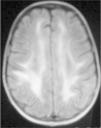

Observación ClínicaCaso 1La paciente es una niña de 7 años diagnosticada de leucemia linfoblástica aguda de alto riesgo con infiltración algodonosa en la retina en el momento del diagnóstico y normalidad del líquido cefalorraquídeo y resonancia magnética (RM) cerebral. Se inicia tratamiento con vincristina, altas dosis de metotrexato, daunorrubicina, ciclofosfamida, corticoides y triple terapia intratecal. A los 14 días apreciamos una aplasia grave medular con signos de toxicidad de grado IV en la mucosa oral, anal y vaginal, íleo paralítico con enterocolitis mucosanguinolenta y lesiones cutáneas. Comienza con deterioro neurológico progresivo, convulsiones, somnolencia y ausencia de respuesta a estímulos, con pérdida de visión. En dos ocasiones, se detecta aumento de presión arterial (PA) con cifras de 140/95. El electroencefalograma muestra ondas lentas difusas, y la RM revela áreas hiperintensas focales bilaterales, con afectación de cerebelo (figs. 1, 2 y 3). Se suspende la quimioterapia y se inicia radioterapia de globos oculares (12 Gy) y craneoespinal (18/12 Gy) por sospecha de infiltración leucémica del sistema nervioso central (SNC).

Ante la sospecha de LEPR, se deben realizar pruebas de imagen, en especial, RM ya que es la técnica radiológica más sensible para la demostración del edema cerebral y puede evidenciar lesiones pequeñas y focales no demostradas con la tomografía. Suele observarse alteraciones de la sustancia blanca supratentorial e infratentorial de límites poco definidos consecuencia del edema cerebral. También puede verse afectación cortical con borrado de surcos y alteraciones en otras zonas, como la afectación cerebelosa de nuestra primera paciente. La RM mostraría en secuencias T1 una señal hipointensa, y en T2, FLAIR y densidad protónica, hiperintensa. Deben incluirse imágenes de difusión de la RM, interesantes desde el punto de vista diagnóstico, pero sobre todo pronóstico, que permite distinguir el edema vasogénico del citotóxico. El edema vasogénico en región posterior es la anormalidad de imagen clásicamente descrita y se asocia a un proceso reversible con pronóstico favorable por lesiones isquémicas precoces. En contraste, la progresión del edema vasogénico a citotóxico es un hallazgo atípico e indicativo de irreversibilidad, ya que implica conversión a infarto e incluso hemorragia cerebral2,14.